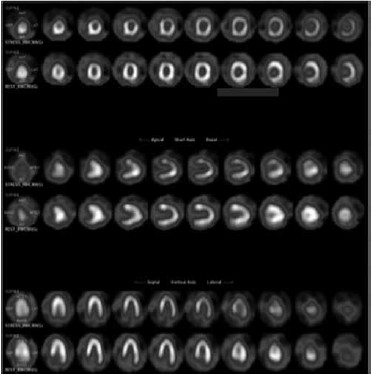

Mulher, 60 anos, tabagista e hipertensa, apresenta dor torácica atípica e teste ergométrico positivo para isquemia. Realiza a cintilografia a seguir:

(Arquivo pessoal; imagem usada com autorização)

É correto afirmar que exame indica